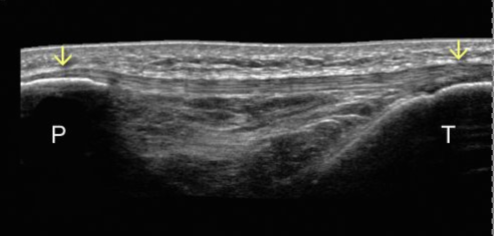

bicep tendon

P = patella

T = tibia

Patellar tendon in middle connect both patella and tibia

also helps connect quad muscles to knee and allow leg to straighten